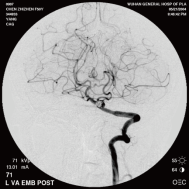

右侧颈内动脉后交通动脉瘤栓塞术前 左椎动脉造影 示左椎动脉夹层动脉瘤: 左椎动脉发出小脑后下动脉处呈囊性扩张,动脉瘤远端血管狭窄

颈内动脉创伤性假性动脉瘤覆膜支架治疗前后(三维像是术前) 右侧颈内动脉后交通动脉瘤栓塞术后完全闭塞

弹簧圈栓塞后造影示左椎动脉夹层动脉瘤消失, 左椎动脉、 多发动脉瘤夹闭术前、术中

左侧小脑后下动脉循环通畅